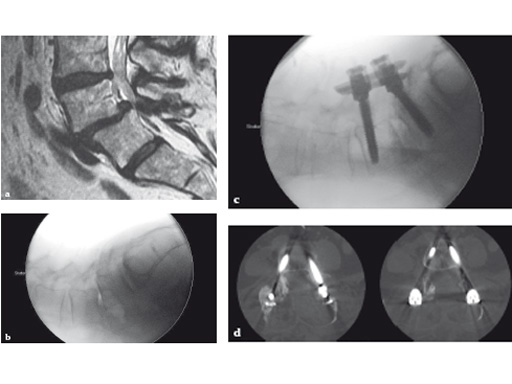

Fig 5ad a Preoperative MRI scan: significant spondylolisthesis in a symptomatic patient.

b Intraoperative x-ray of same patient:

progression to grade II spondylolisthesis in prone position on OR table.

c Minimally invasive surgery allowed decompression, discectomy, instrumentation, and reduction in this patient through two small skin incisions with minimal blood loss.

d Postoperative CT scan: accurate positioning of instrumentation. 3-D-nav allowed for optimization of screw length and diameter given the patients anatomy.